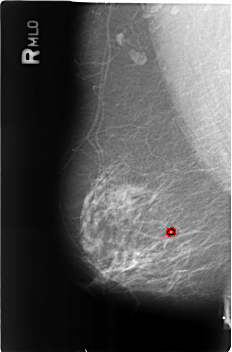

FILE: B_3182_1.RIGHT_MLO.OVERLAY

TOTAL_ABNORMALITIES 1

ABNORMALITY 1

LESION_TYPE CALCIFICATION TYPE COARSE DISTRIBUTION N/A

ASSESSMENT 2

SUBTLETY 3

PATHOLOGY BENIGN_WITHOUT_CALLBACK

TOTAL_OUTLINES 1

BOUNDARY